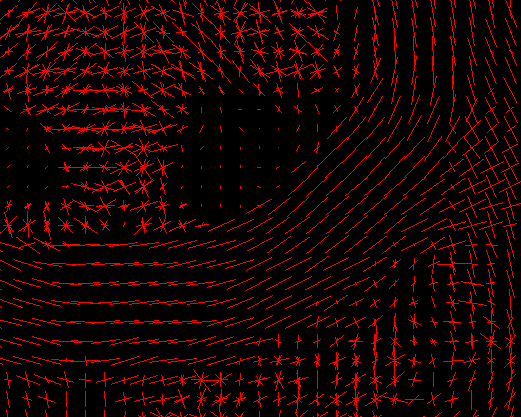

Analysis - Reconstruction

08-10 Tensor reconstruction

11-12 fODF reconstruction

13-14 Tractographies

FA

AD

RD...

CSD PEAKS

NUFO